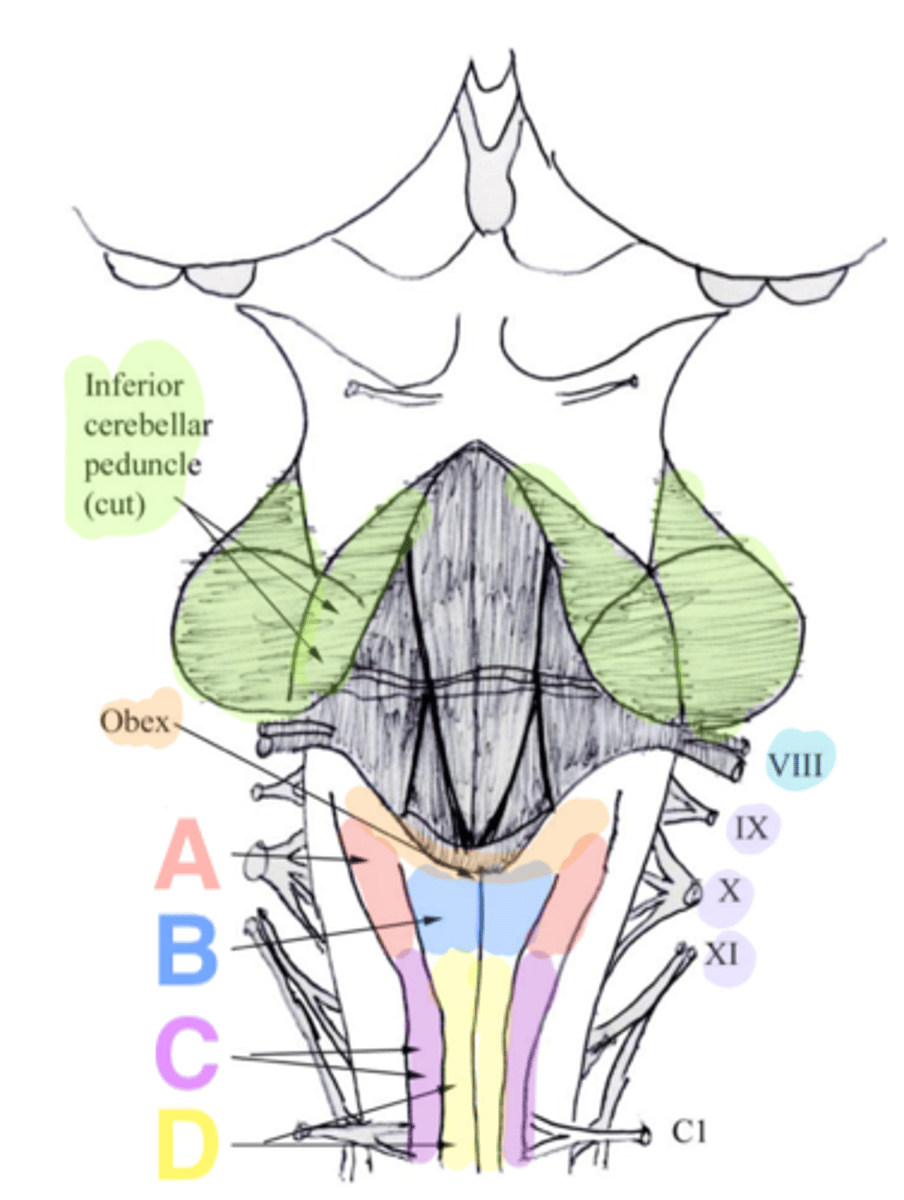

white matter stalks that connect the medulla to the cerebellum

**these help to form the lateral walls of the caudal portion of the 4th ventricle

inferior cerebellar peduncles

V-shaped boundary of the caudal aspect of the 4th ventricle that marks the boundary between the open and closed portions of the medulla

obex

Which cranial nerves arise from the medulla? (and pontomedullary junction)

6-10, 12

inferior cerebellar peduncles

cuneate tubercle

gracilis tubercle

cuneatus tract

gracilis tract

obex